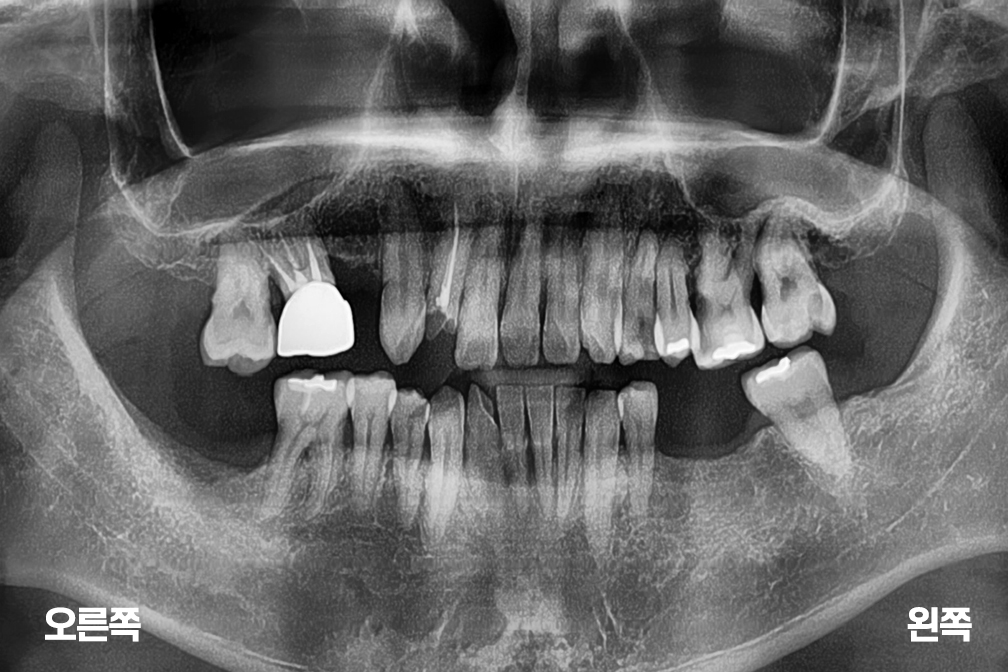

임플란트 오른쪽 위 앞니 임플란트 + 아래 양쪽 임플란트 수술

After 2026년 3월 23일-